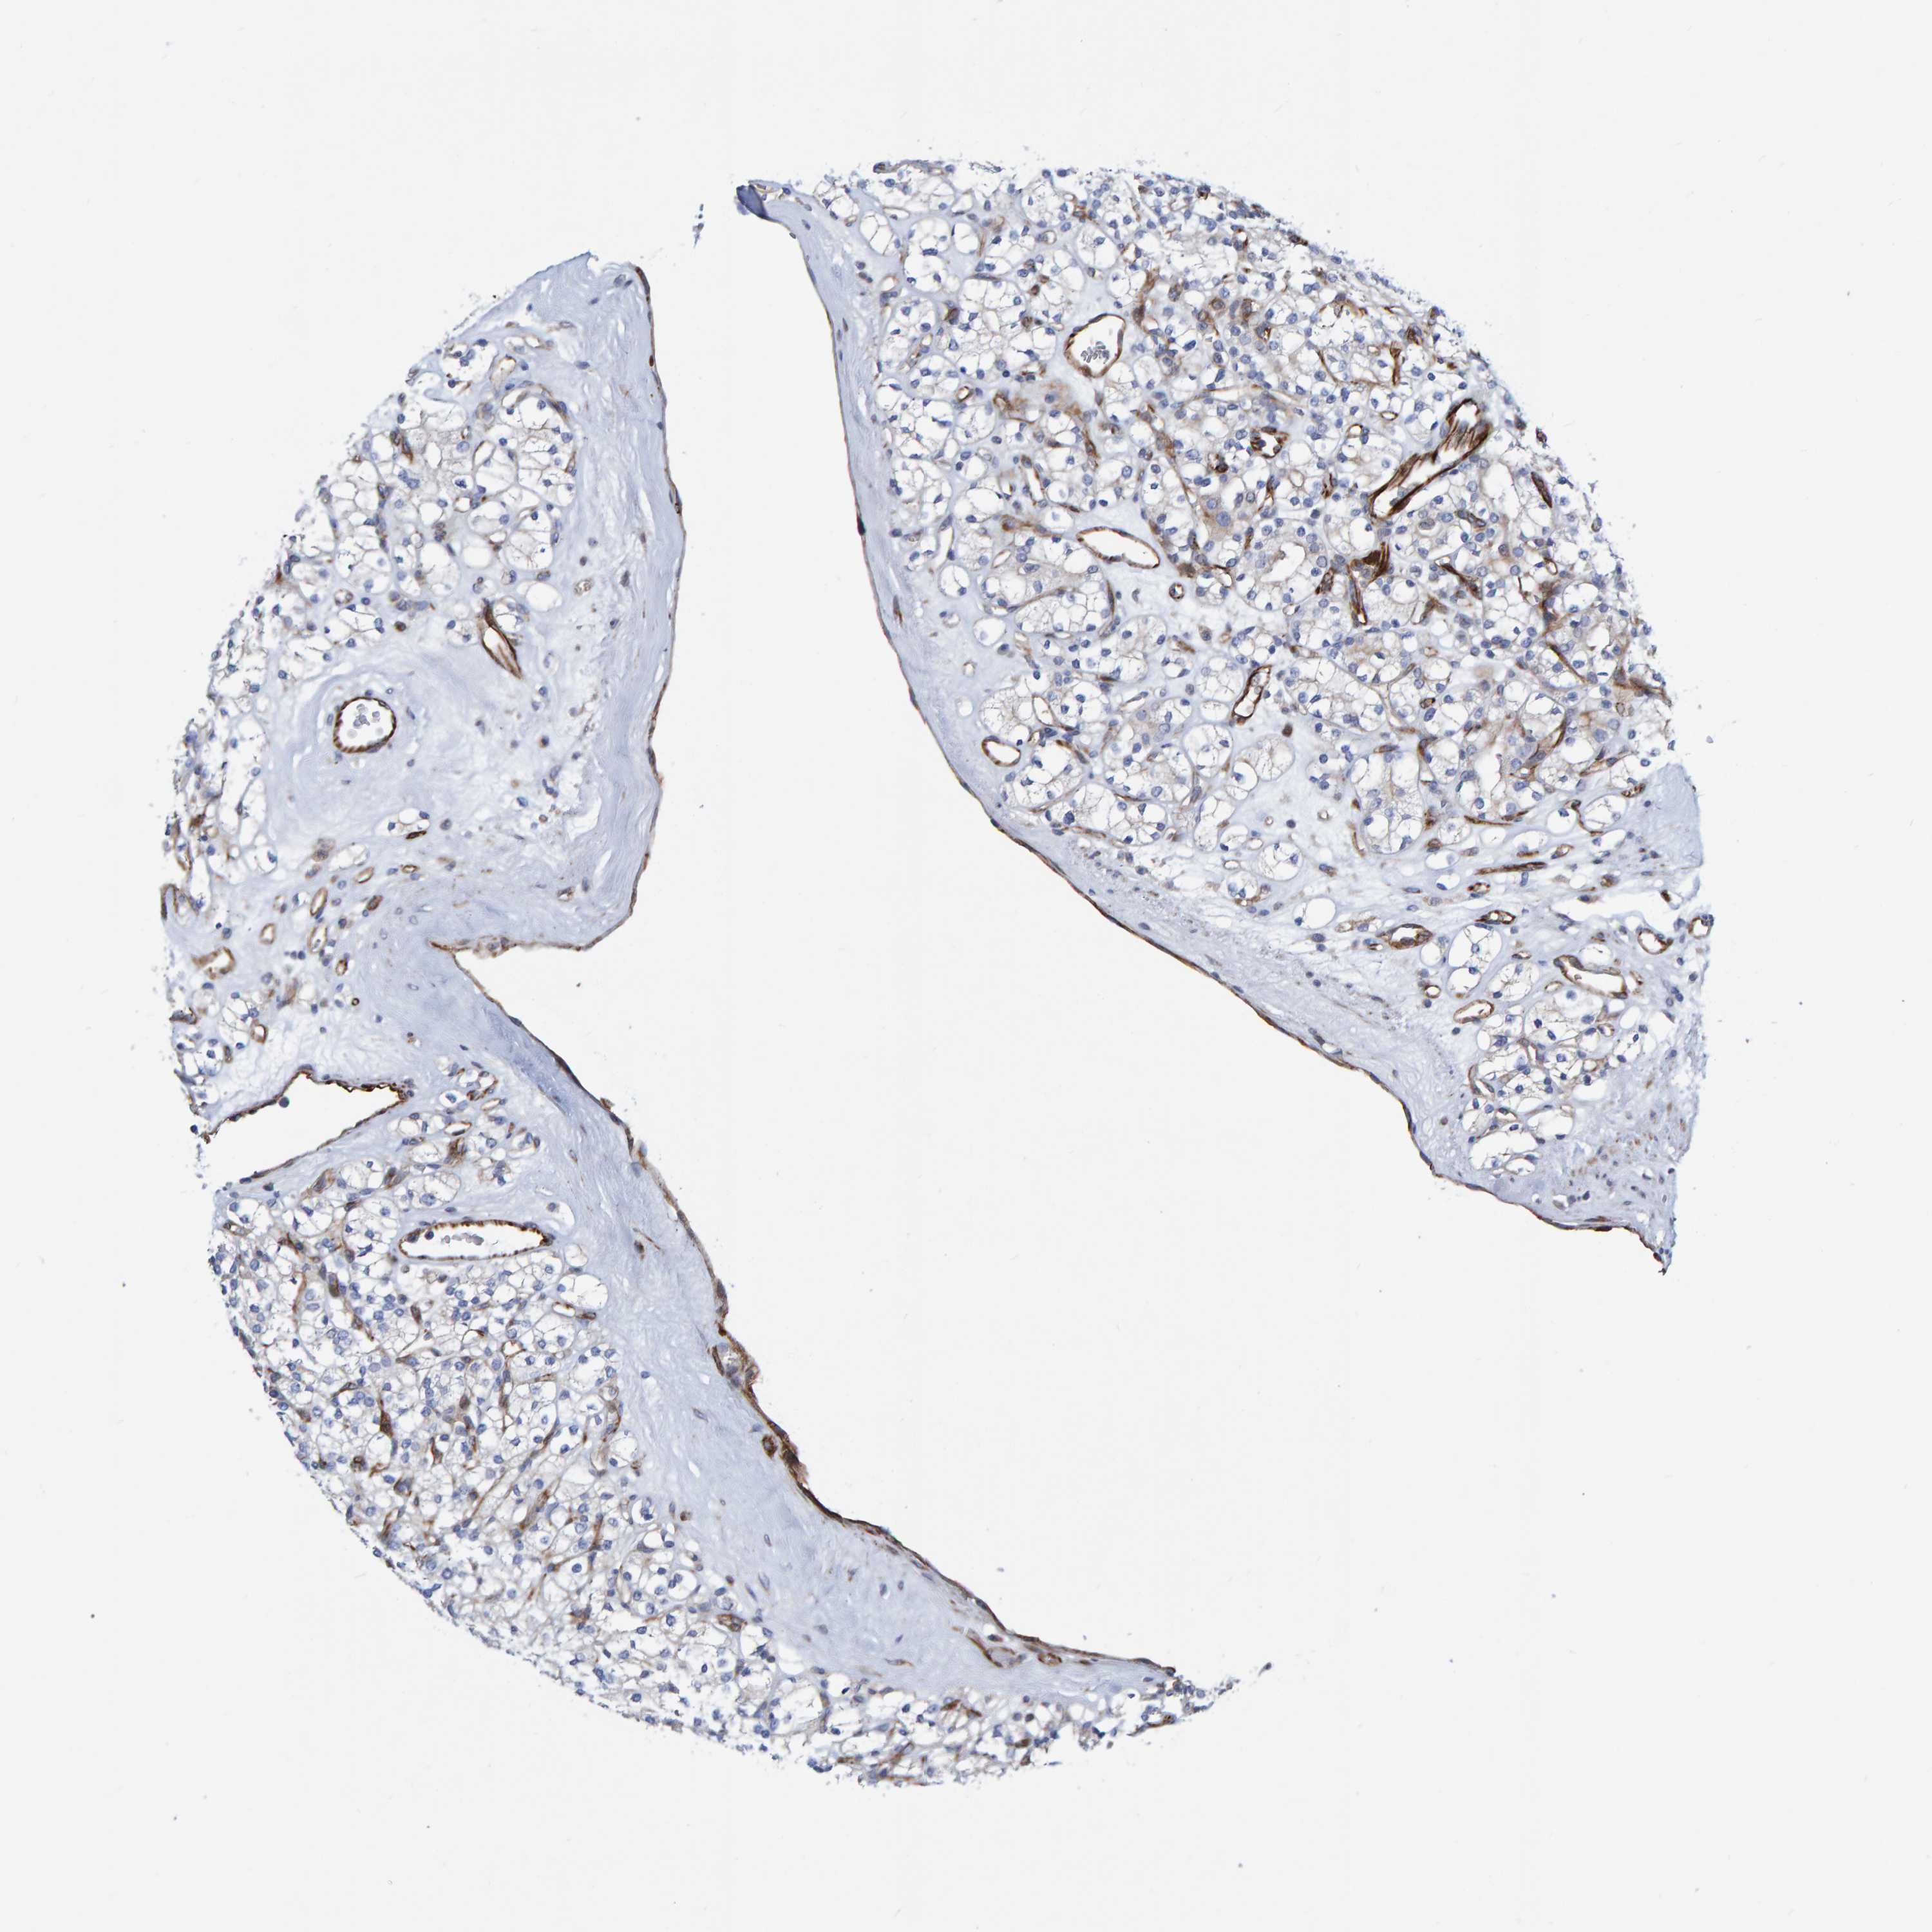

KICH TCGA KIRC TCGA KIRC VALIDATION KIRP TCGA PROTEIN RCC CPTAC PROTEIN EXPRESSION

Renal cancer